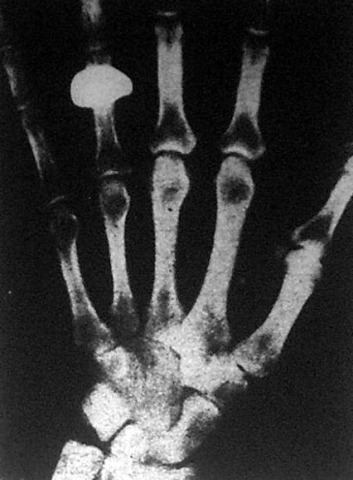

A lámpában keletkező láthatatlan Röngteg-sugarak keresztülhatolnak a lámpa elé tett átlátszatlan tárgyakon és árnyékképet rávetik az ernyőre, amely a sötét Röntgen-szobában jól látható a foszforeszkáló ernyőn. Ha pedig az ernyő helyett fényképlemezt alkalmaznak, ezen pontosan megrögzitődik az a kép, amelyet előbb az ernyő mutatott. Természetesen elsősorban az orvostudomány vette hasznát ennek a kitünő készüléknek.

A sebészorvosok eddig csak kínokat okozó tapogatások segítségével tudták megállapítani a csonttörések pontos helyét s hogy hol fekszenek a test belsejében a veszedelmes daganatok vagy egyéb kóros elváltozások. A Röntgen-képek aztán nagy mértékben elősegítik, hogy a sebész operáló kése biztosan dolgozhasson.

A belgyógyászt is segítik ezek a testen átvilágító sugarak. A súlyosabb esetekben a belgyógyász is Röntgen-képek segítségévéi állapítja meg a szív, tüdő, gyomor, vese, máj és más belső szervek megbetegedéseiből származó elváltozásokat. Igaz, hogy a Röntgen-képek csak árnyképek. Az átvilágított testnek pusztán csak különböző tulajdonságú részeiről nyújtanak felvilágosítást, amelyek különböző mértékben nyelik el a Röntgen-sugarakat.

De azt már nem mutatják, hogy gyulladásban van-e a test vagy miképpen van megtámadva. Az orvosnak csak kitünő segítőeszköz a Röntgen-kép. A gyógyítás azonban a betegség kisérő jelenségei alapján történik. A sebészek és belgyógyászokon kívül ma már a fogorvosok is felhasználják a Röntgen-képeket a fog betegségének pontos megállapítására.